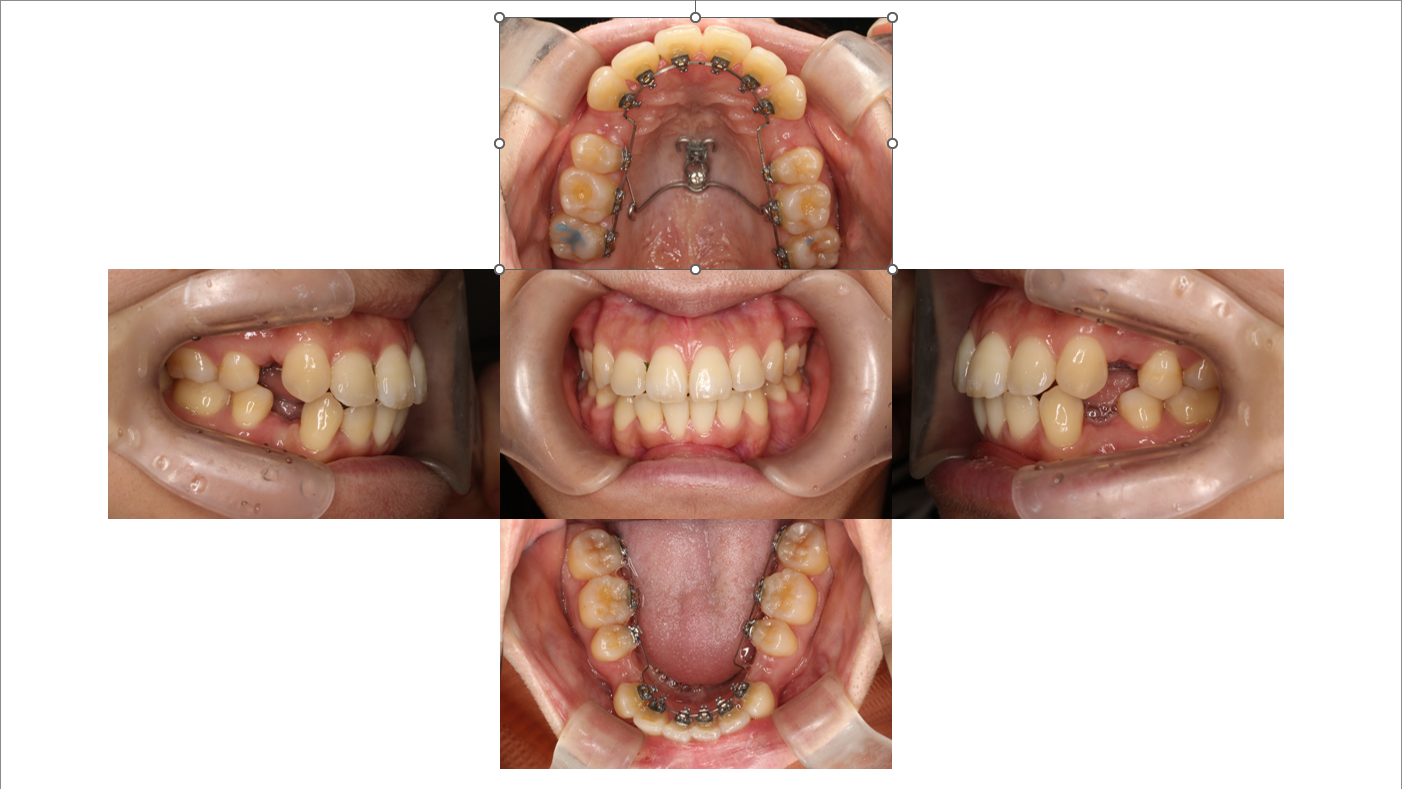

1年

叢生・出っ歯症例

凸凹が取れた後は、目に見えて大きな変化は少なくなってきますが、微調整を行いながら前歯の位置を後ろに下げていきます。

矯正中の方は凸凹が取れてから、大きな変化が少ないので精神的に大変になってくる方が多いです。

少しづつでも最終的な仕上がりに向かって歯は必ず動いているので安心してください。